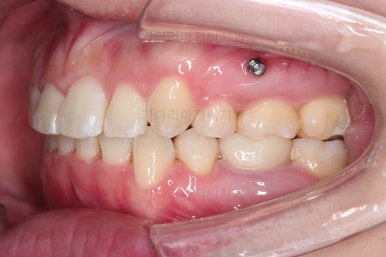

초진 시 입안의 모습입니다.

전반적으로 치열이 삐뚤고, 특정 앞니는 톡 튀어나가 미적으로 좋지 못한 상황이었습니다.

이갈이, 이악물기 습관도 있어서 앞니는 삐뚤어진 채로 치아가 많이 갈려있는 상황이었습니다.